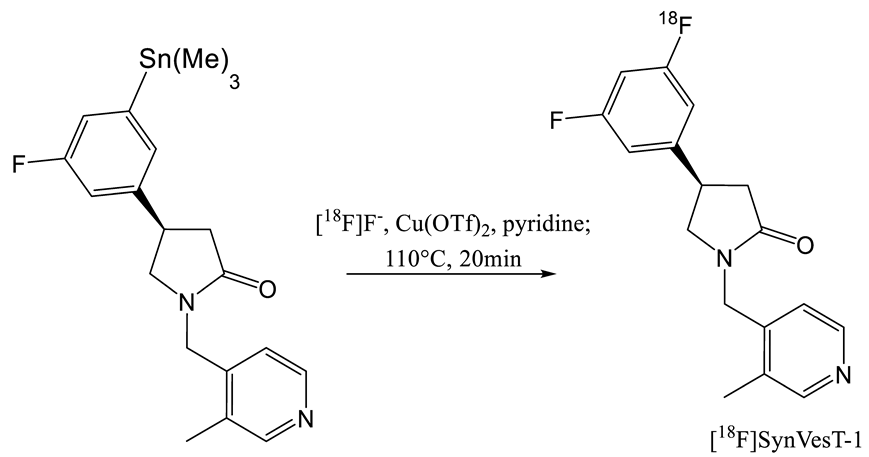

2. Radiochemistry of SV2A PET Radiotracers

- Li, S.; Cai, Z.; Wu, X.; Holden, D.; Pracitto, R.; Kapinos, M.; Gao, H.; Labaree, D.C.; Nabulsi, N.; Carson, R.E.; et al. Synthesis and in Vivo Evaluation of a Novel PET Radiotracer for Imaging of Synaptic Vesicle Glycoprotein 2A (SV2A) in Nonhuman Primates. ACS Chem. Neurosci. 2018, 10, 1544–1554. [Google Scholar] [CrossRef]

- Constantinescu, C.C.; Tresse, C.; Zheng, M.; Gouasmat, A.; Carroll, V.M.; Mistico, L.; Alagille, D.; Sandiego, C.M.; Papin, C.; Marek, K.; et al. Development and In Vivo Preclinical Imaging of Fluorine-18-Labeled Synaptic Vesicle Protein 2A (SV2A) PET Tracers. Mol. Imaging Boil. 2018, 21, 509–518. [Google Scholar] [CrossRef]

- Cai, Z.; Li, S.; Finnema, S.; Lin, S.; Zhang, W.; Holden, D.; Carson, R.; Huang, Y. Imaging Synaptic Density with Novel 18f-Labeled Radioligands for Synaptic Vesicle Protein-2a (Sv2a): Synthesis and Evaluation in Nonhuman Primates. J. Nucl. Med. 2017, 58 (Suppl. S1), 547. [Google Scholar]

- Cai, Z.; Li, S.; Zhang, W.; Pracitto, R.; Wu, X.; Baum, E.; Finnema, S.J.; Holden, D.; Toyonaga, T.; Lin, S.-F.; et al. Synthesis and Preclinical Evaluation of an 18F-Labeled Synaptic Vesicle Glycoprotein 2A PET Imaging Probe: [18F]SynVesT-2. ACS Chem. Neurosci. 2020, 11, 592–603. [Google Scholar] [CrossRef] [PubMed]

| Entry | Tracer | Ref | Synthesis of the Radiotracer | pIC50 for Human SV2A | Ki (nM) for Human SV2A | Molar Activity (GBq. µmol−1) | RCY (%) |

|---|---|---|---|---|---|---|---|

| 1 | [11C]Levetir-acetam | [18] |  | 5.7 [24] | 2500 | 17 | 8.3 (dc) |

| 2 | [18F]UCB-H | [19] |  | 7.8 | 9.0 | 518 | 15 (ndc) |

| 3 | [21] |  | 815 ± 185 | 35 (ndc) | |||

| 4 | [18F]UCB-A | [23] |  | 7.9 [24] | ND a | 65 | 14 (dc) |

| 5 | [11C]UCB-J | [24] |  | 8.2 | 1.5 | 215 | 35 (dc) |

| 6 | [18F]UCB-J | [27] |  | Similar to [11C]UCB-J | Similar to [11C]UCB-J | 59 ± 36 | 1–2 (ndc) |

| 7 | [18F]SynVesT-1 | [28,29] |  | 8.4 | 2.2–4.7 b | 242 | 19 (ndc) |

| 8 | [18F]SynVesT-2 | [31] |  | ND a | 12 | 141 | 7(dc) |

| 9 | [18F]1 | [33] |  | 8.3 | ND a | 40–80 | 1.5 (dc) |